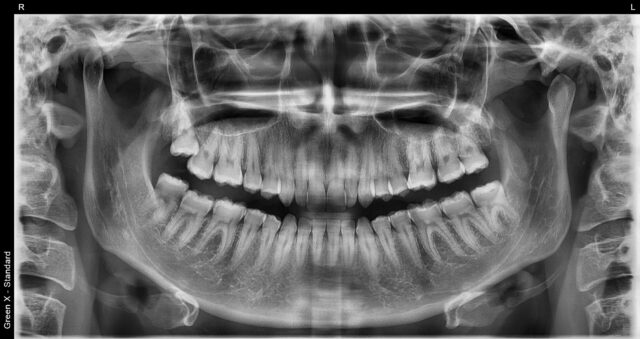

- Pantomogram (OPG) — przegląd całej szczęki i żuchwy.

Przegląd, ortodoncja, kwalifikacja do leczenia: pantomogram (OPG).

RTG punktowe pozwala ocenić wierzchołki korzeni i jakość wypełnień. Pantomogram daje szeroki obraz obu łuków. CBCT 3D umożliwia dokładną analizę kanałów, resorpcji, ubytków kości i planowanie implantów. Wynik i omówienie dostajesz na miejscu.